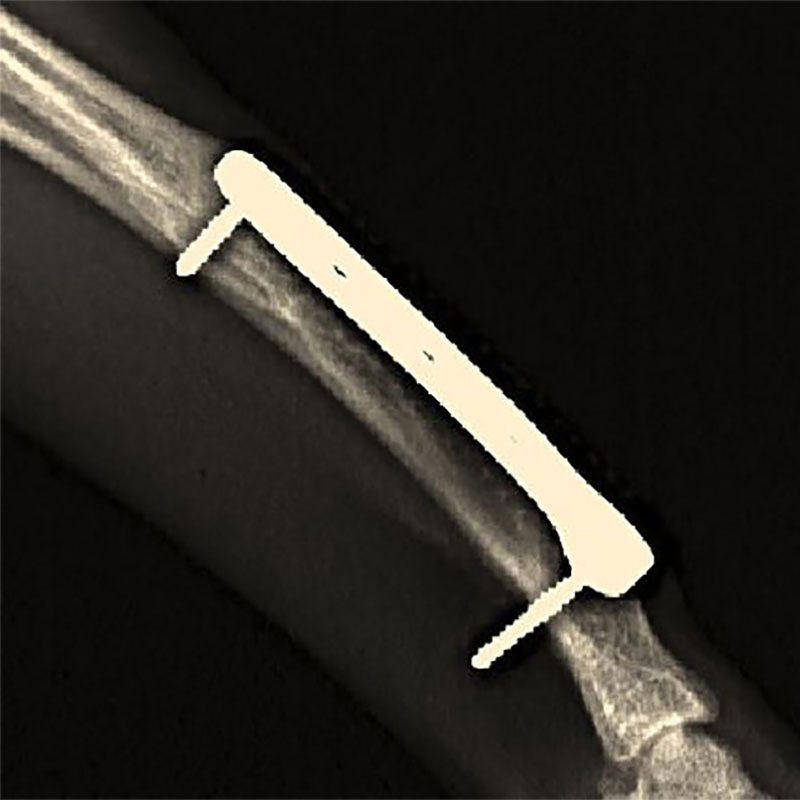

プレート法による再骨折誘発事例

細い骨にプレートを入れることは難易度が非常に高く、技術的なアピールは最高ですが、技術と治療は違います。

プレートなど体内に金属を入れる危険性

プレート法の問題点

・骨折部位への血流の遮断

・骨折時の様々な生体反応の抑制

・強固な固定が、仮骨の形成を抑制

・骨とプレートとの弾性率の違いが、体重負荷によりさらに顕在化